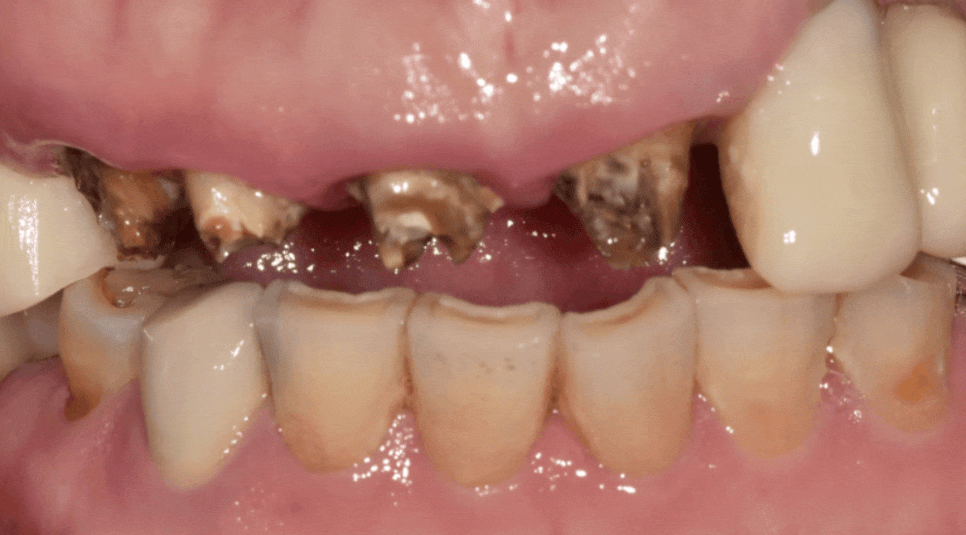

얼마 전, 3년 전에 하셨던

앞니 브릿지(#13~21)가 갑자기 빠져서

놀란 마음으로 내원하신 환자분이 계셨습니다.

251020

평소 양치할 때 피가 나긴 했지만

통증이 없어 대수롭지 않게 생각하셨다고 해요.

빠진 브릿지를 제거하고 입안을

살펴보니 상황이 생각보다 좋지 않았는데요,

앞니 4개 모두 충치가 깊게 진행되어

검게 삭아버린 상태였고,

CT 상으로 확인한 오른쪽 위 송곳니(#13)는

뿌리 끝 염증으로 잇몸뼈까지 녹아있었죠.

환자분께서는 다시 씌우기를 원하셨지만,

이미 충치 부위를 제거하고 나면

남아있는 치아량이 거의 없었습니다.

이런 상태에서 억지로 기둥을 세워 씌운다 해도,

뿌리 끝 염증이 다시 문제를 일으키면

애써 만든 보철물을 금방 못 쓰게 될 게 뻔하죠...

장기적으로 보았을 때

환자분께 결코 좋은 선택이 아니었기에

재부착은 힘들다고 솔직하게 말씀드렸습니다.